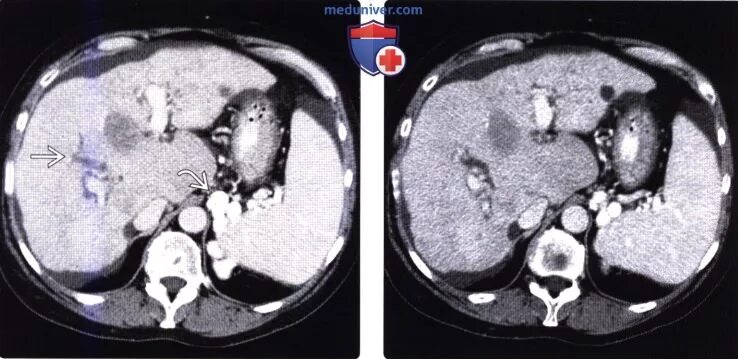

Цирроз на кт